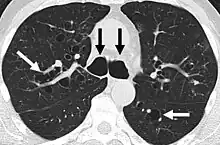

A chest x-ray is abnormal in most patients with bronchiectasis. Computed tomography is recommended to confirm the diagnosis and is also used to describe the distribution and grade the severity of the disease. Radiographic findings include airway dilation, bronchial wall thickening, and atelectasis.[66] There are three types bronchiectasis that can be seen on CT scan, namely cylindrical, varicose, and cystic bronchiectasis.[67]

- Bronchiectasis primarily in the middle lobe of the right lung.

- Bronchiectasis secondary to a large carcinoid tumor (not shown) that was completely obstructing the bronchus proximally. Dilation of the airways is present.